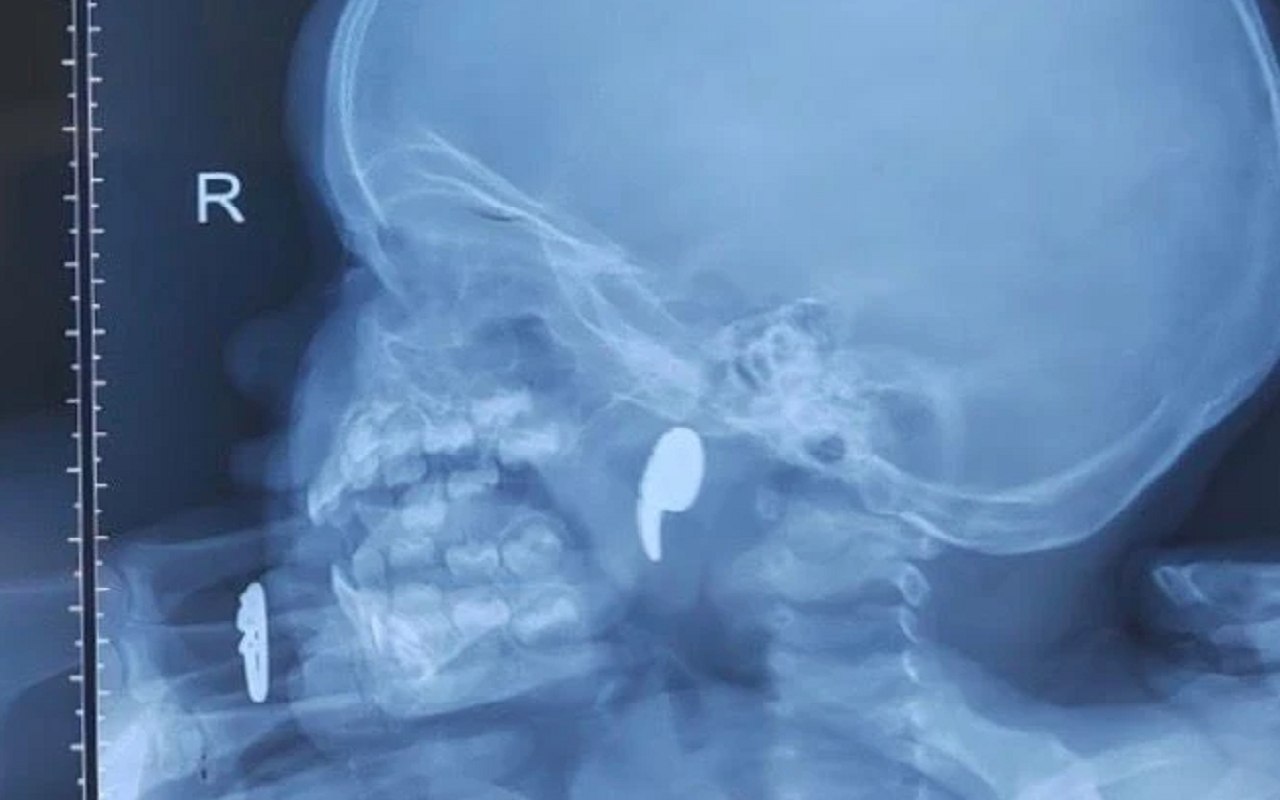

По словам родителей малышки, ребенок жаловался на боль в горле, отказывался от еды, при этом у девочки наблюдалось активное слюнотечение. Оказалось, что ребенок играл с магнитом в виде запятой и внезапно начала давиться. Мама попыталась извлечь его самостоятельно, но он сместился в носоглотку.

Юной пациентке сделали операцию под общей анестезией и удалили опасный предмет под эндоскопическим контролем. Спустя сутки девочку выписали домой под наблюдение педиатра.